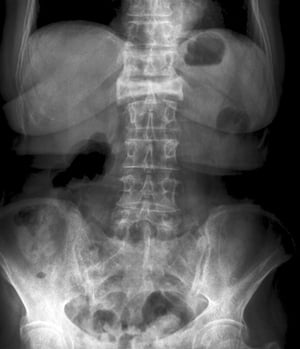

Diese Kompressionsfraktur des 1. Lendenwirbels ist in der anteroposterioren Ansicht als starker Höhenverlust und erhöhte Radiodichte sichtbar.

Diese Kompressionsfraktur des 1. Lendenwirbels ist in der anteroposterioren Ansicht als starker Höhenverlust und erhöht

ZEPHYR/SCIENCE PHOTO LIBRARY